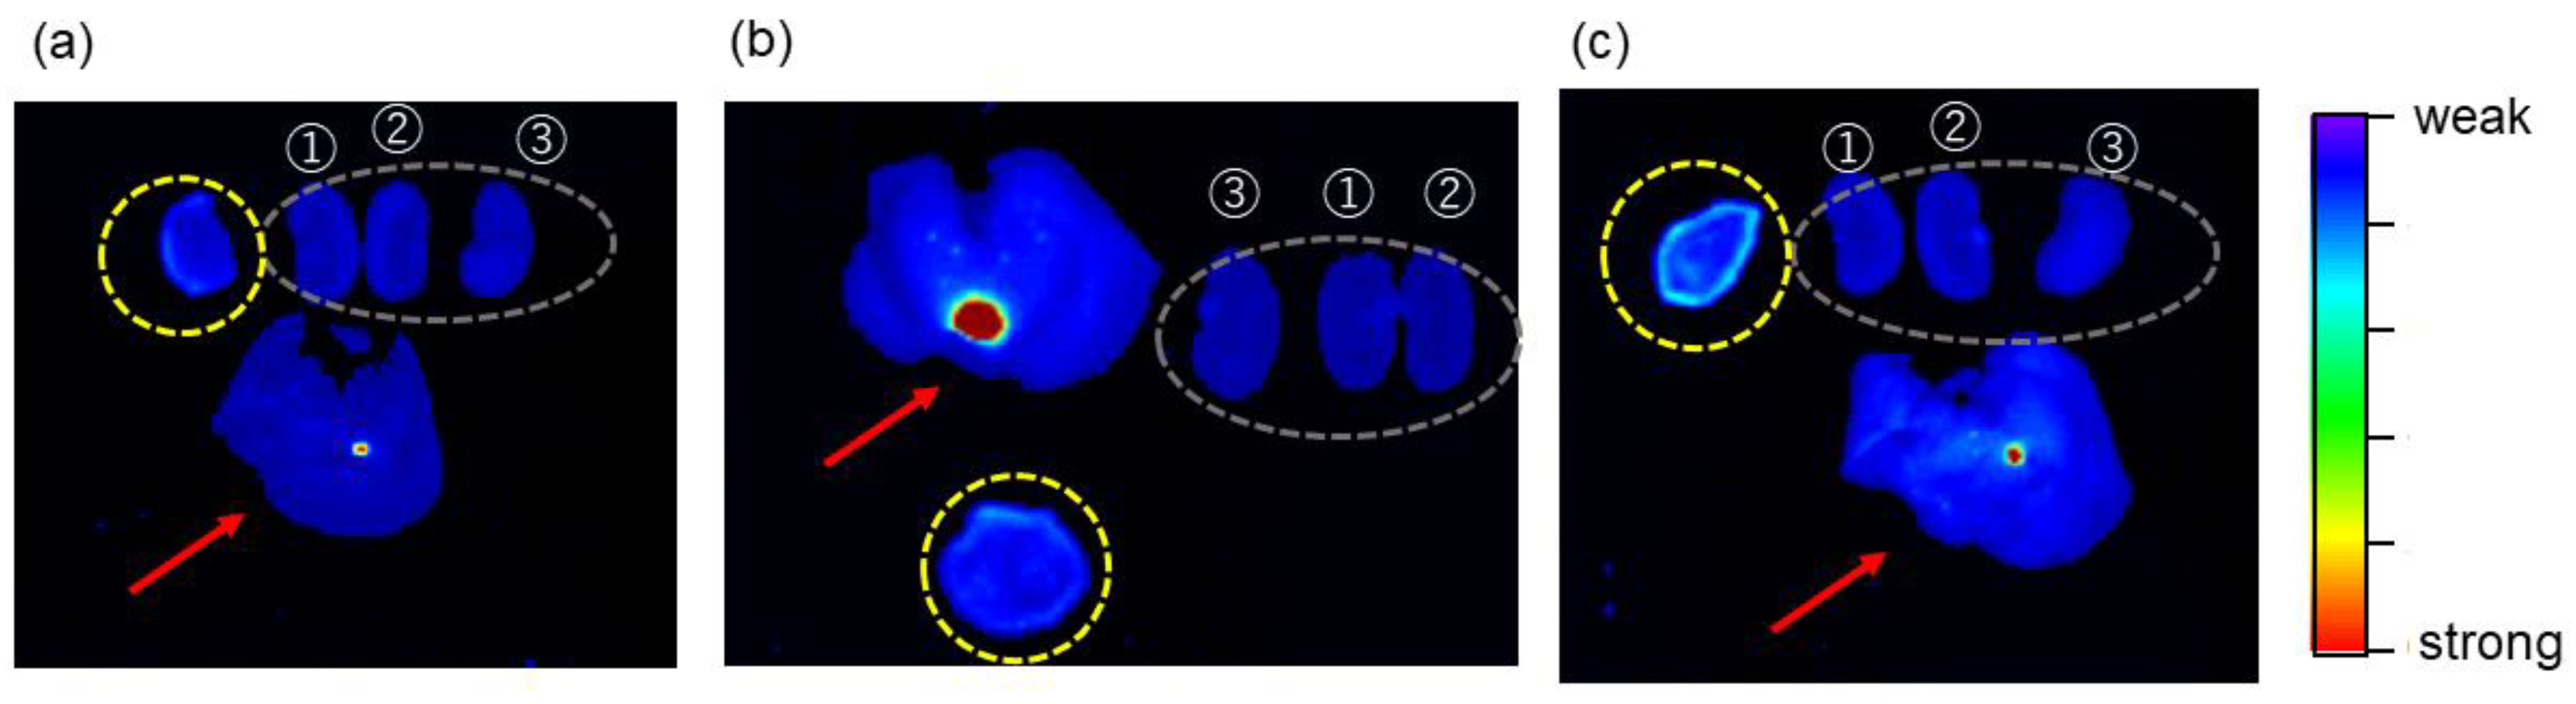

2.6. Tumor-Imaging with TFMAQ-diEg4

- (1)

- Single-injection of 2.0 mM TFMAQ-diEg4 in saline, via the tail vein, without local heat.

- (2)

- Single-injection of 2.0 mM TFMAQ-diEg4 in saline, via the tail vein, with local heat.

- (3)

- Single-injection of 2.0 mM TFMAQ-diEg4 in saline, via the tail vein and drip via the tail vein, with local heat.

- (4)

- Single-injection of 0.2 mM TFMAQ-diEg4 in saline, via the tail vein and drip, without local heat.

- (5)

- Single-injection of 0.2 mM TFMAQ-diEg4 in saline, via the tail vein and drip with local heat.

| Groups * | 1 | 2 | 3 | 4 | 5 |

|---|---|---|---|---|---|

| Concentration of the vial | 2.0 mM | 2.0 mM | 2.0 mM | 0.2 mM | 0.2 mM |

| Concentration in the body # | 0.5 mM | 0.5 mM | Over 1.0 mM | Over 0.1 mM | Over 0.1 mM |

| Heat at tumor | No | Yes | Yes | No | Yes |

| Intravenous (i.v.) administration via the tail vein | Single-i.v. of 200 μL | Single-i.v. of 200 μL | Single-i.v. of 200 μL and then drip of 100 μL/h for 2 h | Single-i.v. of 200 μL and then drip of 100 μL/h for 2 h | Single-i.v. of 200 μL and then drip of 100 μL/h for 2 h |

| Emission intensity | Weak ** | Weak ** | Strong | Weak | Weak |